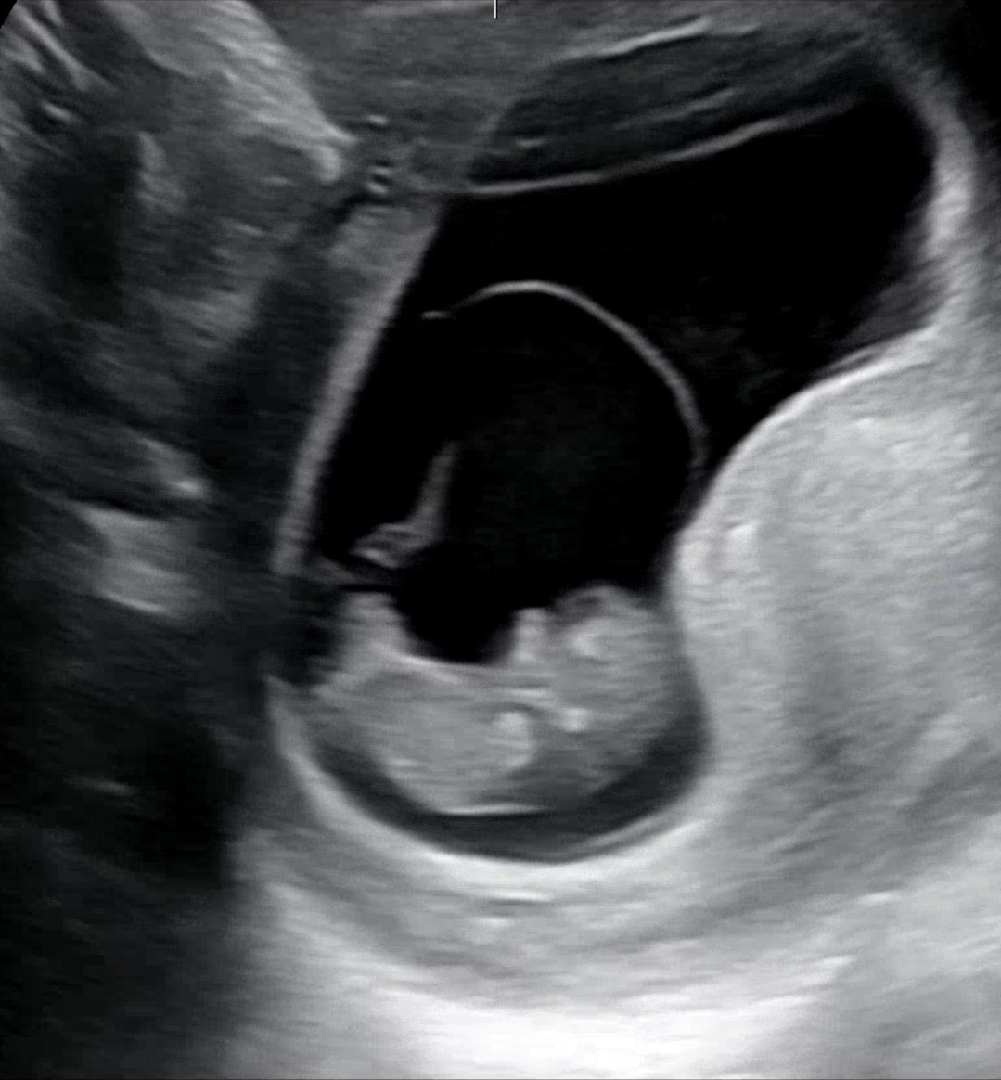

10주 0일차 하리보

요번에 니프티 하려고 채혈도 했는데 부디 문제 없었으면 좋겠네요 🫢